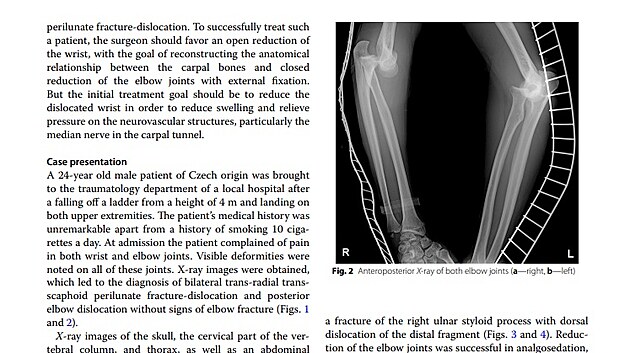

„Jedná se o raritní úraz, který nebyl dosud ve světové literatuře popsán. U pacienta, který spadl ze čtyřmetrového lešení, došlo ke zlomeninám a vykloubení obou zápěstí a vykloubení obou loketních kloubů,“ popsal operatér úrazu Jaroslav Pilný. Poraněný muž byl do nemocnice v Novém Městě na Moravě převezen z jiného zdravotnického zařízení.